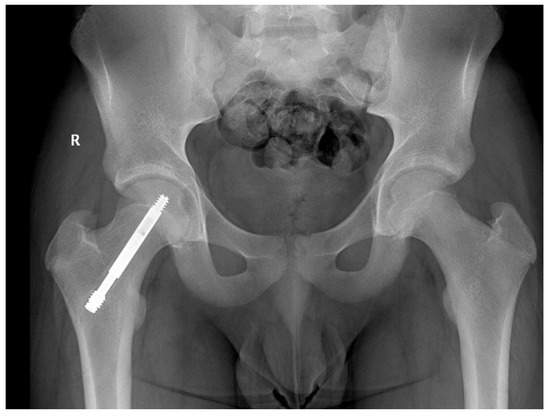

In two cases, at 16 months postoperatively we observed screw failure (entire screw slipped) Figure 2, most likely due to accidental crossings with the drill through the growth cartilage, and of an insufficient number of threads passed through the physis (three). No patient having at least four threads passed over the physis presented with slippage or no telescoping of the screw.

Figure 2.

Male patient, 9 years old, slipped screw at 16 months follow-up.